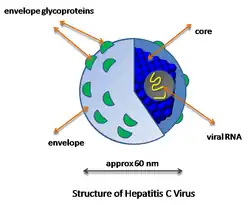

Viral hepatitis

Viral hepatitis is the most common type of hepatitis worldwide, especially in Asia and Africa.[27] Viral hepatitis is caused by five different viruses (hepatitis A, B, C, D, and E).[18] Hepatitis A and hepatitis E behave similarly: they are both transmitted by the fecal–oral route, are more common in developing countries, and are self-limiting illnesses that do not lead to chronic hepatitis.[18][28][29]

Hepatitis B, hepatitis C, and hepatitis D are transmitted when blood or mucous membranes are exposed to infected blood and body fluids, such as semen and vaginal secretions.[18] Viral particles have also been found in saliva and breastmilk. Kissing, sharing utensils, and breastfeeding do not lead to transmission unless these fluids are introduced into open sores or cuts.[30] Many families who do not have safe drinking water or live in unhygienic homes have contracted hepatitis because saliva and blood droplets are often carried through the water and blood-borne illnesses spread quickly in unsanitary settings.[31]

Hepatitis B and C can present either acutely or chronically.[18] Hepatitis D is a defective virus that requires hepatitis B to replicate and is only found with hepatitis B co-infection.[18] In adults, hepatitis B infection is most commonly self-limiting, with less than 5% progressing to chronic state, and 20 to 30% of those chronically infected developing cirrhosis or liver cancer.[32] Infection in infants and children frequently leads to chronic infection.[32]

Unlike hepatitis B, most cases of hepatitis C lead to chronic infection.[33] Hepatitis C is the second most common cause of cirrhosis in the US (second to alcoholic hepatitis).[34] In the 1970s and 1980s, blood transfusions were a major factor in spreading hepatitis C virus.[33] Since widespread screening of blood products for hepatitis C began in 1992, the risk of acquiring hepatitis C from a blood transfusion has decreased from approximately 10% in the 1970s to 1 in 2 million currently.[18]

Viral hepatitis

The pathway by which hepatic viruses cause viral hepatitis is best understood in the case of hepatitis B and C.[18] The viruses do not directly activate apoptosis (cell death).[18][60] Rather, infection of liver cells activates the innate and adaptive arms of the immune system leading to an inflammatory response which causes cellular damage and death, including viral-induced apoptosis via the induction of the death receptor-mediated signaling pathway.[18][60][61][62] Depending on the strength of the immune response, the types of immune cells involved and the ability of the virus to evade the body's defense, infection can either lead to clearance (acute disease) or persistence (chronic disease) of the virus.[18] The chronic presence of the virus within liver cells results in multiple waves of inflammation, injury and wound healing that over time lead to scarring or fibrosis and culminate in hepatocellular carcinoma.[60][63] People with impaired immune response are at greater risk of developing chronic infection.[18] Natural killer cells are the primary drivers of the initial innate response and create a cytokine environment that results in the recruitment of CD4 T-helper and CD8 cytotoxic T-cells.[64][65] Type I interferons are the cytokines that drive the antiviral response.[65] In chronic Hepatitis B and C, natural killer cell function is impaired.[64]